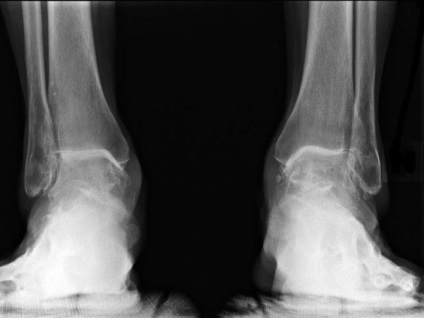

Examinarea arată o mică mobilitate limitată picior. diagnostic precis poate fi făcută doar după o examinare cu raze X. Imaginea prezintă reducerea subtilă în dimensiunea spațiului comun. Există o creștere patologică a țesutului osos pe lateral, din față sau din spate a suprafeței articulare.

Radiografia arată o reducere semnificativă în lumenul spațiului comun, în valoare de 40%. De multe ori se dezvoltă subchondral scleroză țesutului osos.

Deoarece procesele atrofice mișcare progres limitat în mușchi, în special cele situate în apropierea gleznei. imagine cu raze X arată suprapunerea aproape completă a spațiului comun.

Înainte de a începe tratamentul, pacienții supuse unor teste de diagnostic. Metoda principală de diagnostic - radiografie. Dacă este necesar, mai multe informații este atribuit CT.